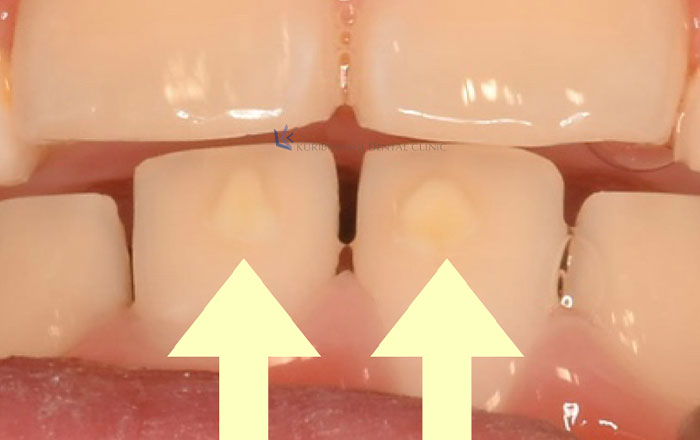

5.乳歯・永久歯に突起が付いている

最後に、ホワイトスポットという状態ではない、最初から歯の形が違うことで、白く見えてしまうことがあるものをご紹介します。

乳歯・永久歯に歯が生えた時点で突起が付いていることがあり「カラベリー結節」「中心結節」など、状態によって名前が異なります。

この状態は、歯の形のため問題ないものです。

ですが、むし歯になるリスクが高い状態のため、歯医者さんに定期的に通うなどの経過観察が必要です。